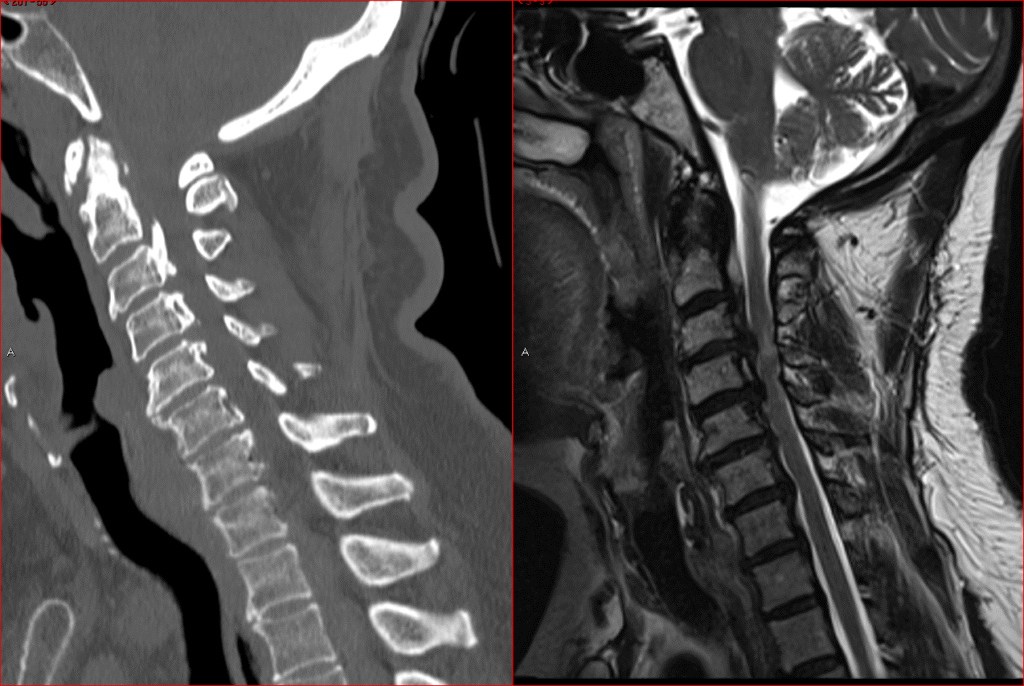

Posterior Cervical Spine Surgeries

Posterior Cervical Fusion